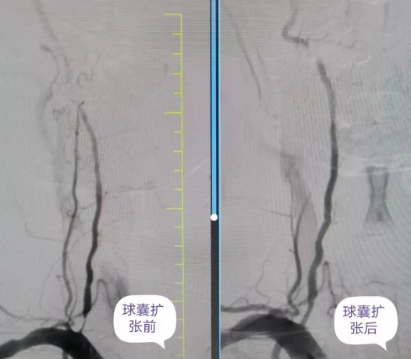

品質(zhì)國(guó)文丨精準(zhǔn)微創(chuàng) 打通大腦“生命線” ——椎動(dòng)脈球囊擴(kuò)張成形術(shù)

近日,國(guó)文醫(yī)院公主嶺院區(qū)神經(jīng)介入科丁金明主任、朱洪波副主任帶領(lǐng)團(tuán)隊(duì)為一位右側(cè)椎動(dòng)脈起始段重度狹窄患者行球囊擴(kuò)張成形術(shù),成功開通幾近閉塞血管,打通患者“生命通道”,該項(xiàng)技術(shù)自開展以來已為本地區(qū)眾多動(dòng)脈狹窄患者帶來福音。 閱讀量:1270

品質(zhì)國(guó)文 | 精準(zhǔn)“疏堵”,為生命“通路”——椎動(dòng)脈狹窄球囊擴(kuò)張術(shù)

家住內(nèi)蒙古的閆大哥,近三個(gè)月來飽受頭暈困擾,反復(fù)住院治療卻無明顯好轉(zhuǎn),癥狀逐漸加重,甚至出現(xiàn)走路不穩(wěn)的情況。慕名來到長(zhǎng)春國(guó)文醫(yī)院后,經(jīng)過詳細(xì)檢查,發(fā)現(xiàn)閆大哥左側(cè)椎動(dòng)脈已經(jīng)閉塞 閱讀量:1272